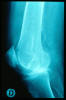

APR Fractura bimaleolar de tobillo